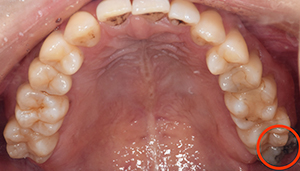

口腔内

- Before

- After

半埋伏の親知らずでした。3糸縫合しました。